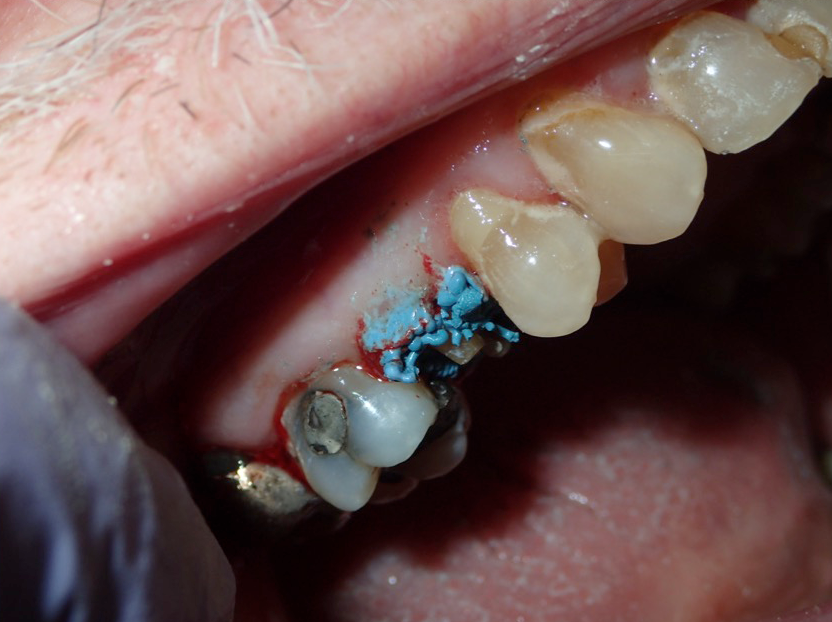

Figure 6 through Figure 9 demonstrate the use of retraction paste and a cap. An upper bicuspid was prepared (Figure 6), and some bleeding occurred due to the clinician working below the existing restorations. Retraction paste was then applied (Figure 7), but there was still some residual bleeding. The clinician then had the patient close on the retraction cap to stop the bleeding (Figure 8). Some blanching occurred as the patient bit into the cap. The patient will hold that position depending on how much bleeding occurs. Figure 9 shows the exposed margin ready for impressioning. In this case, the retraction cap was kept in place with the patient biting down on it for 2 to 3 minutes instead of 1 to 2 minutes because there was a fair amount of bleeding initially.

Fig 8. Cotton retraction cap in place.

Figure 8